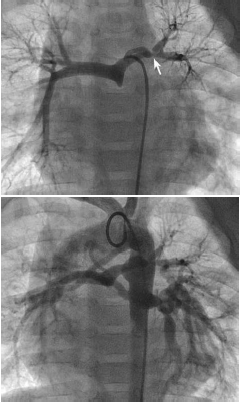

Um recém-nascido é levado a cateterismo cardíaco para melhor definição diagnóstica. Após observar as seguintes imagens, conclui-se que

Provas